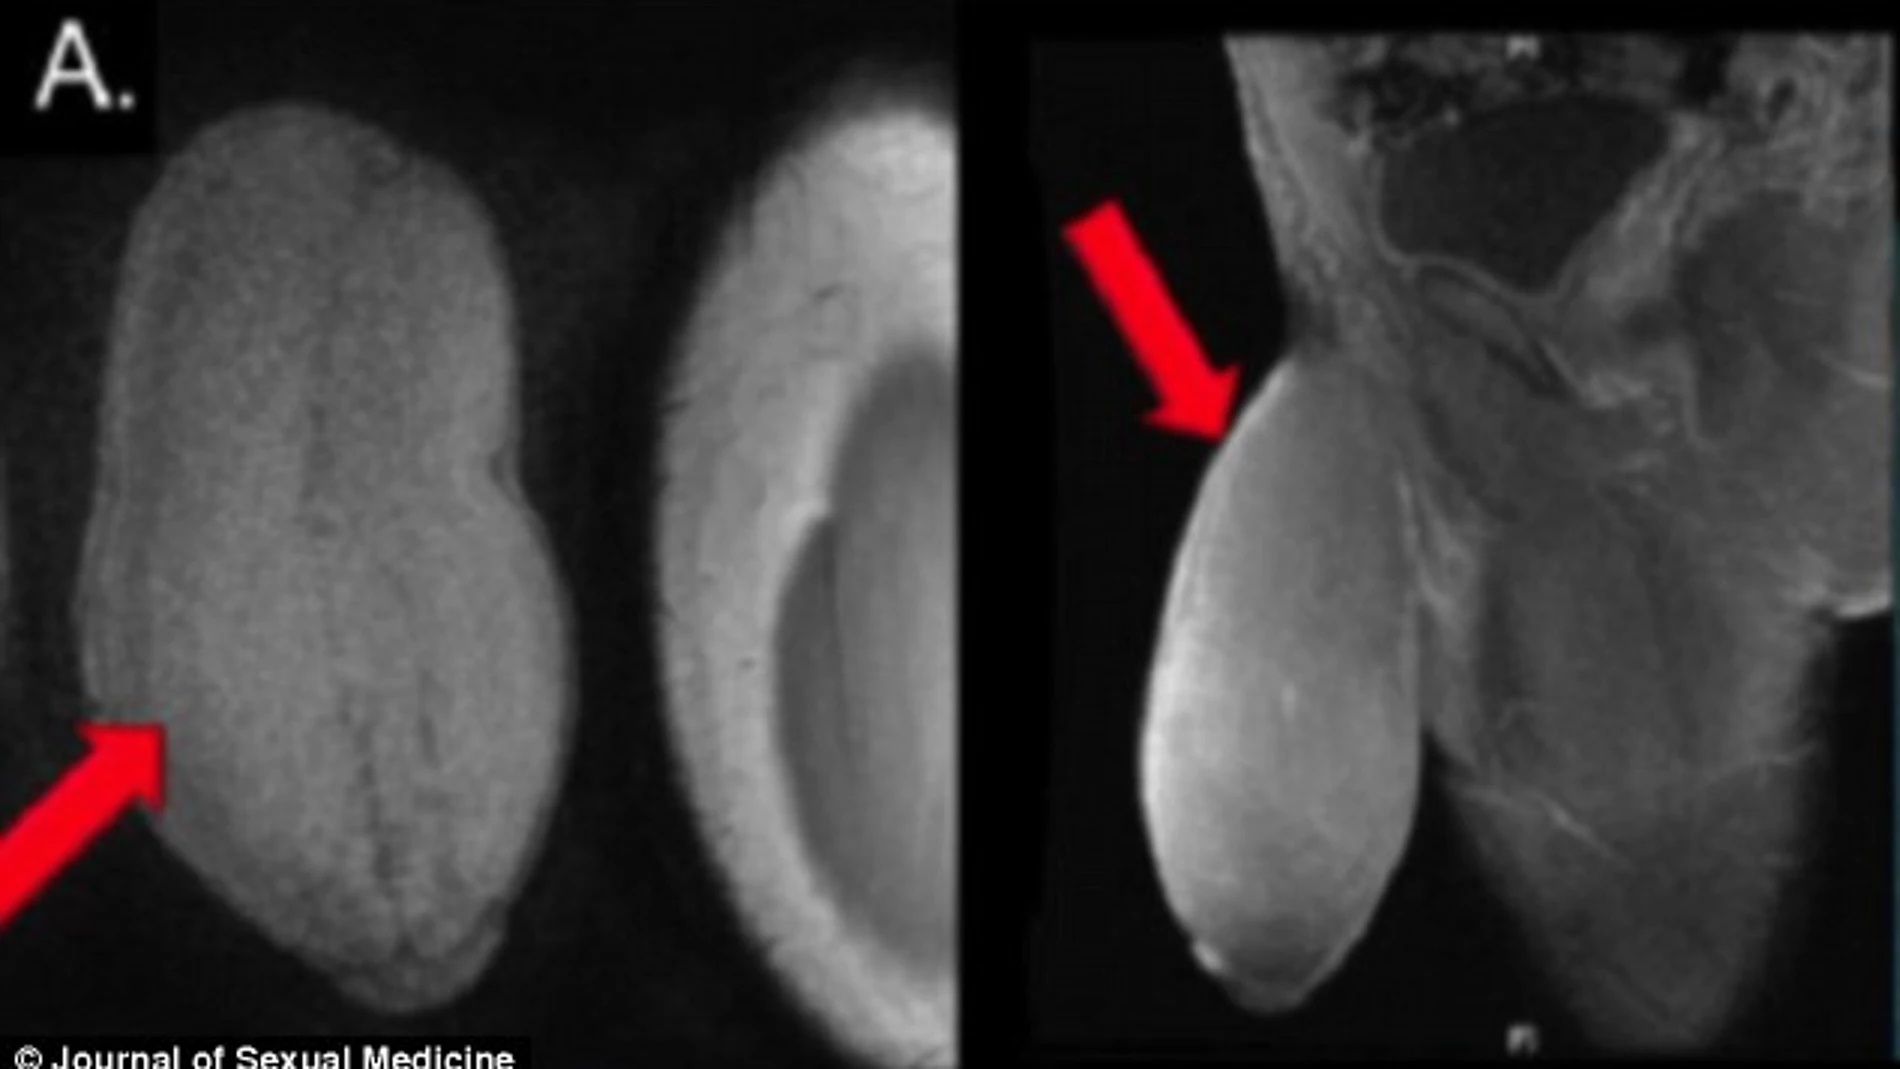

Los episodios de priapismo habían hinchado y deformado su pene hasta el punto de adoptar una forma similar a la de un 'pomelo', tal y como aseguró el doctor. "Su pene era tan grande que cuando tenía erecciones no crecía, simplemente se endurecía". "Su pene se había hinchado como un globo", sostuvo Carrión.

El equipo médico que realizó la intervención no encontró ningún precedente que les orientara. Finalmente adoptaron una técnica quirúrjica utilizada para tratar la enfermedad de Peyronie, una condición en la que el tejido cicatrizal invade el pene causando que se doble.